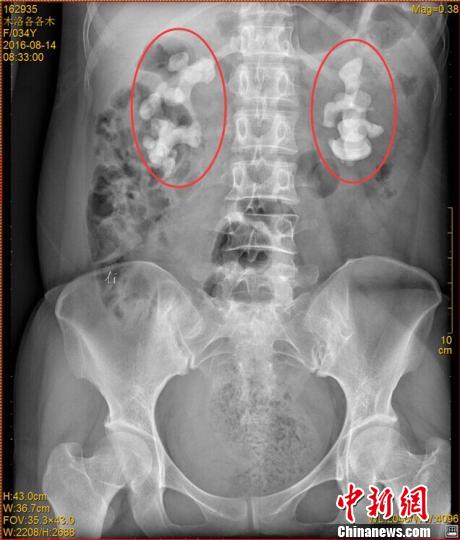

各各木術(shù)前影像圖片,紅圈內(nèi)為巨大腎結(jié)石。 鐘欣 攝

中新網(wǎng)成都11月7日電 (王鵬)記者7日從四川省結(jié)石病醫(yī)院獲悉,該醫(yī)院近日收治了一名罕見腎結(jié)石病人。來自四川涼山的34歲女子各各木,雙腎長(zhǎng)出10厘米巨型結(jié)石,腎內(nèi)空間幾乎全被結(jié)石填滿。

“臨床上,雙腎長(zhǎng)巨大結(jié)石的患者一般都是中老年男性,女性較為少見,年輕女性更加罕見。”四川省結(jié)石病醫(yī)院常立高醫(yī)生詳細(xì)檢查后發(fā)現(xiàn),該女子雙腎內(nèi)空間幾乎被結(jié)石全部填滿。他詢問患者后判斷,該罕見病例的出現(xiàn)與女子常年喝生水有直接關(guān)系。